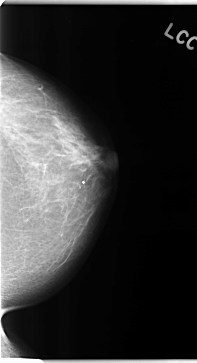

C_0110_1.LEFT_CC

LEFT_CC LINES 4712 PIXELS_PER_LINE 2552 BITS_PER_PIXEL 12 RESOLUTION 50 NON_OVERLAY